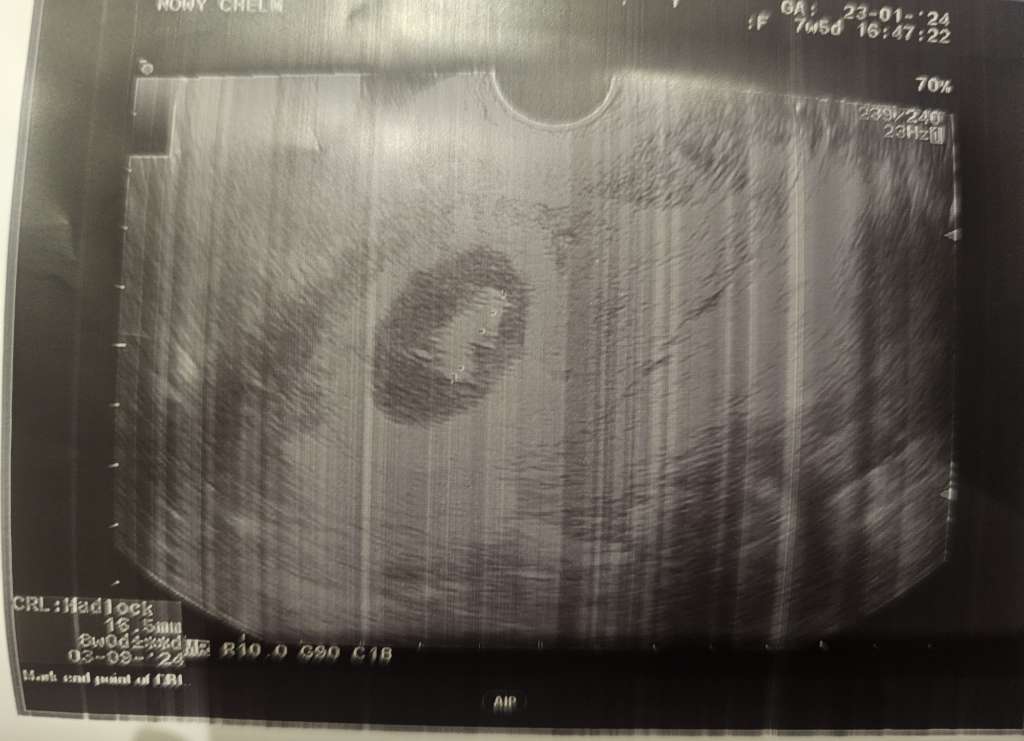

Ja już po wizycie, wszystko w porządku, bąbel ma już 16,5mm i ładnie bije serduszko :)

Zdjęcie z nfz wyraźne jak nie wiem 😂

Btw. Obraz z USG kojarzy mi się z tą emojka 🗿